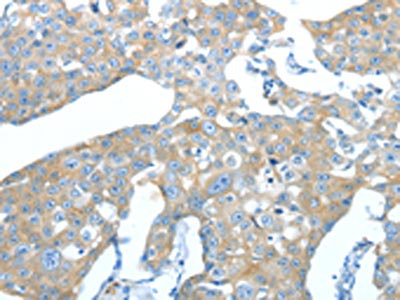

The image on the left is immunohistochemistry of paraffin-embedded Human liver cancer tissue using CSB-PA068489(AMPH Antibody) at dilution 1/25, on the right is treated with fusion protein. (Original magnification: ×200)

The image on the left is immunohistochemistry of paraffin-embedded Human breast cancer tissue using CSB-PA068489(AMPH Antibody) at dilution 1/25, on the right is treated with fusion protein. (Original magnification: ×200)